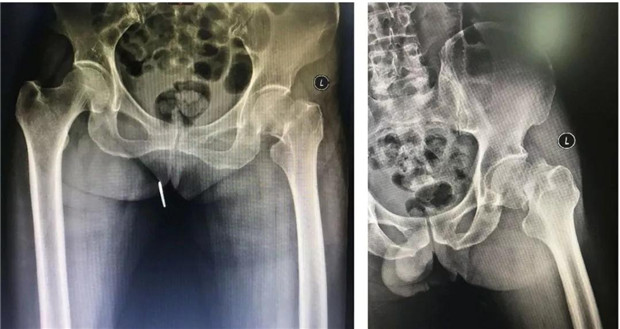

股骨颈骨折

人工全髋关节置换术后